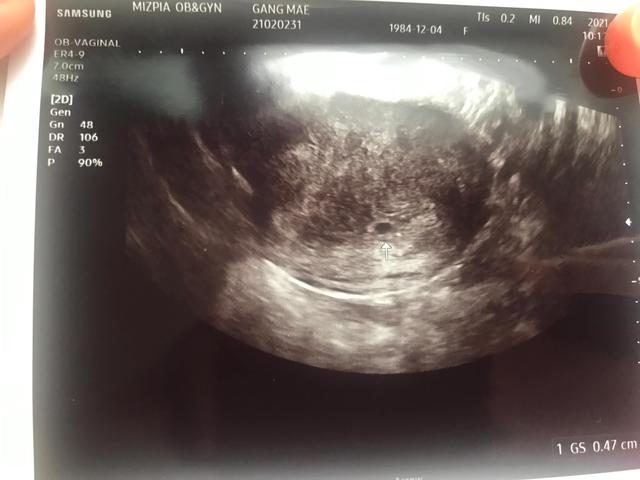

18号b超检查发现孕囊还很小,自然就担心了。